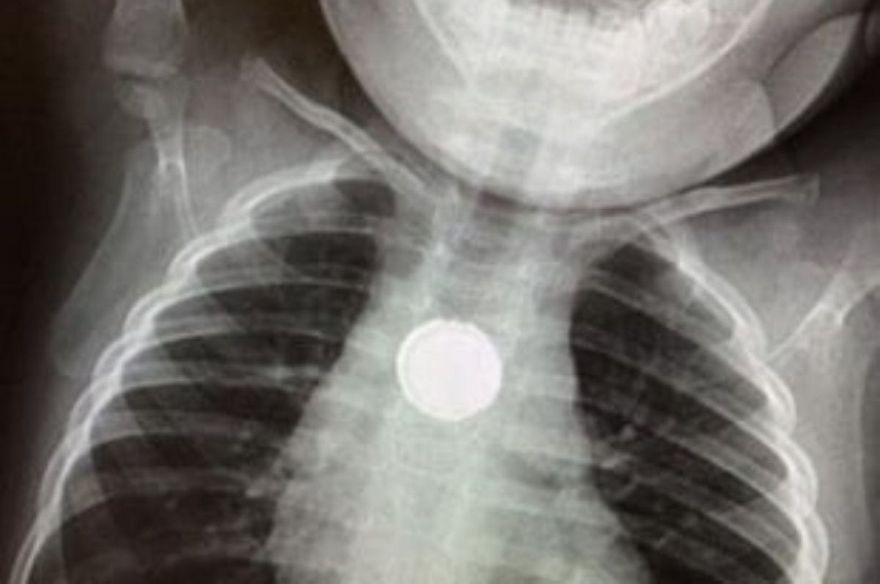

Батарейка провела в пищеводе ребенка полтора часа, но успела вступить в реакцию со слизистой пищевода.

Как сообщил в Facebook врач-эндоскопист Днепровской детской областной клинической больницы Сергей Щудро, батарейка была обнаружена в пищеводе ребенка. Специалисты произвели эндоскопию и посторонний предмет был изъят. Малыша обследовали на четвертые сутки после инцидента и обнаружили дефекты слизистой в месте, где была батарейка, врачи оставили его под наблюдением.